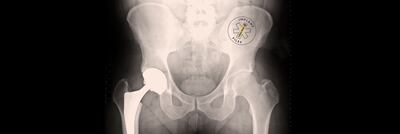

As part of its coverage, The Irish Times published a major report on the DePuy metal hip, which was introduced in 2004 and withdrawn in 2010. There are currently more than 1,000 cases before the High Court from Irish patients seeking damages arising from the controversial new product.

The hip was recalled after data from the National Joint Registry for England, Wales, Northern Ireland and the Isle of Man showed it was failing in a higher percentage of patients than other types of hip replacement products.

“In Ireland, an estimated 3,500 people had received this [DePuy] implant following hip replacement surgery, the highest usage of this implant per capita in the world.

“As there was no national implant register in place at that time, hospitals had to undertake a lengthy review of all theatre diaries and patient charts to identify patients who may have received these implants. This process took years in some instances.”

The organisation, established to create sustainable clinical audit programmes at national level, said the global recall of the DePuy hip highlighted the need for a national register for such implants.

The Irish National Orthopaedic Register (INOR) monitors the safety of implants and if an episode such as that of the DePuy hips now occurred, information about recipients would be available in minutes rather than months or years, Noca said in a statement.